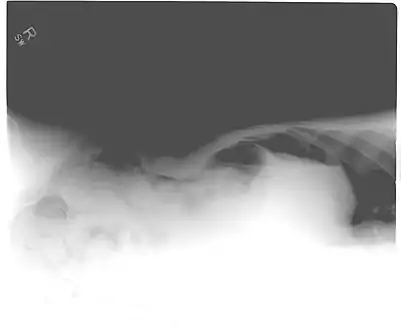

When present, pneumoperitoneum can often be seen on projectional radiography, but small amounts are often missed, and CT scan is nowadays regarded as a criterion standard in the assessment of a pneumoperitoneum.[18] CT can visualize quantities as small as 5 cm³ of air or gas.

Signs that can be seen on projectional radiography are shown below: